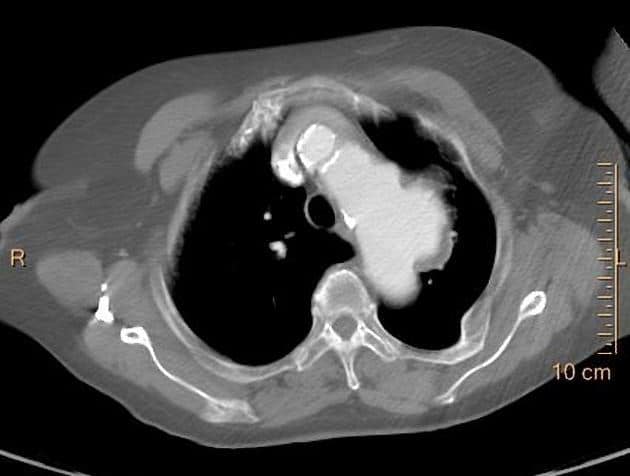

Phình ĐM chủ ngực - Ảnh 4

Phình ĐM chủ ngực

» Thông tin: Nam giới – 65 tuổi.

» Lâm sàng: Đau ngực.